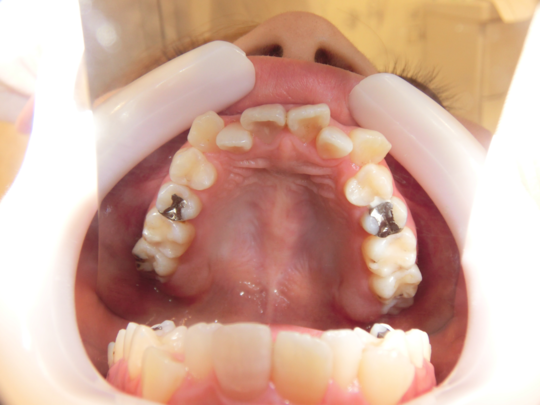

治療前

治療説明 歯科矯正でも目立ちにくい矯正方法であるマウスピース矯正で治療しました

治療期間 2年6か月

治療費用498000 円